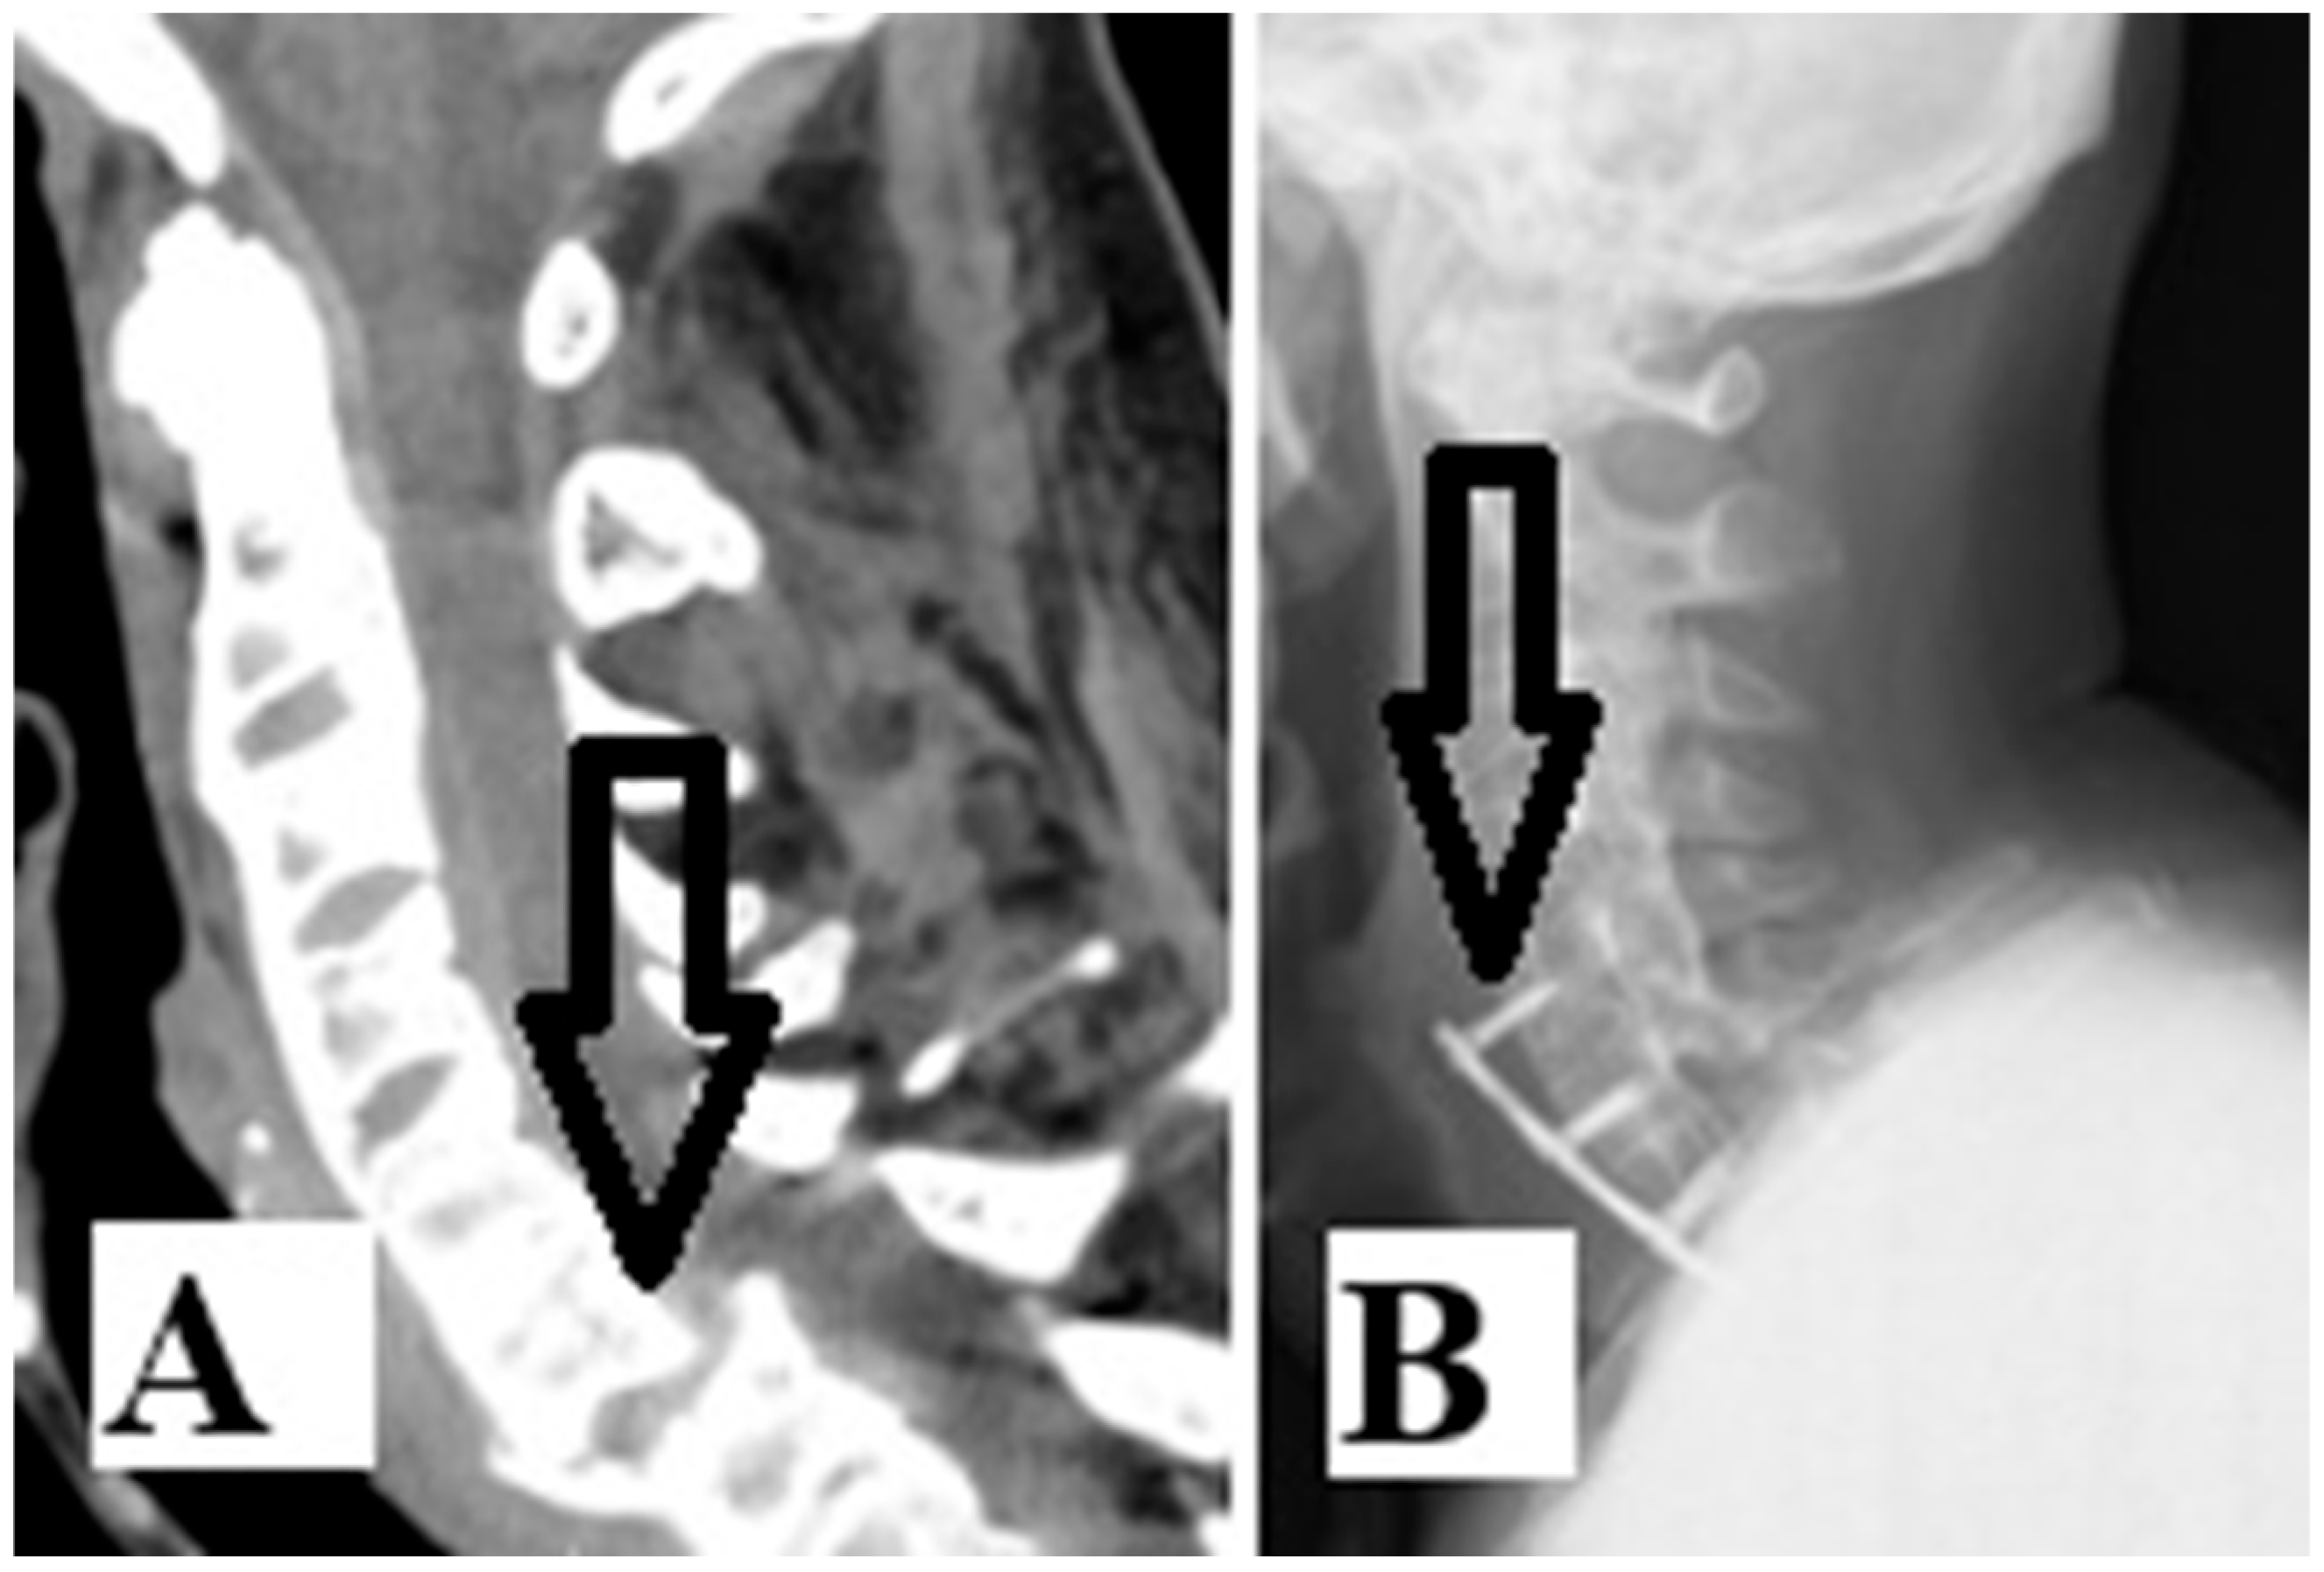

From another aspect, according to the same search engines and with the addition of the words “esophageal injury”, only three cases of AS with esophageal injury [8,9,10] emerged in the last ten years (Table 1). Injury of the esophagus is a rare but serious complication when cervical spine fracture occurs in patients with AS. There are two possible mechanisms of esophageal injury: direct or acute injury or delayed injury after hardware failure. Our patient had luxation fracture at the C6–C7 level (Figure 2A). He first underwent Crutchfield traction and anterior C5-T1 fixation with a titanium plate. Six months after surgery, the patient underwent re-surgery due to hardware failure and esophageal injury (Figure 2B). Further radiologic examination should be performed to confirm these devastating injuries (Figure 2B and Figure 3A).

Figure 2. Sagittal CT scan (A) revealed a luxation fracture at the C6–C7 level (arrow). Follow-up X-rays scan after six months (B) revealed hardware failure (arrow), which led to the esophagus injury.